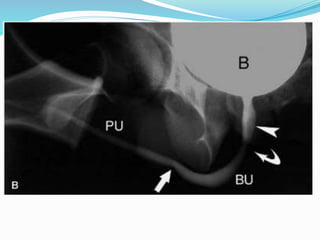

Normal antegrade urethrogram . The mild areas of narrowing and dilation are

normal. On an antegrade study, unlike a retrograde examination, the proximal

urethral is distended and readily assessed. No evidence of stricture or

extravasation is seen.

Normal antegrade urethrogram. The mild areas of narrowing and dilation are normal. On an antegrade study, unlike a retrograde examination, the proximal urethral is distended and readily assessed. No evidence of stricture or extravasation is seen.